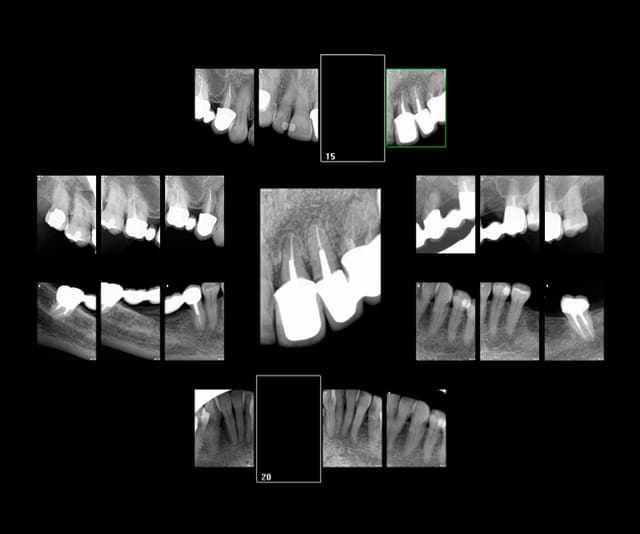

Ma grand mère est ma seule patiente qui a atterri aux urgences à cause d'une hémorragie suite à une extraction. Et voilà le genre de conneries qu'on fait pour lui remplacer son Stellite qu'elle ne supportait plus à 89 ans car très fortement diminuée. En croisant les doigts pour que ca ne se casse pas la gueule.

Il a tenu jusqu'à sa mort à 92 ans. All on 4. -)

Capture d e cran 2016 03 18 07.56 - Eugenol